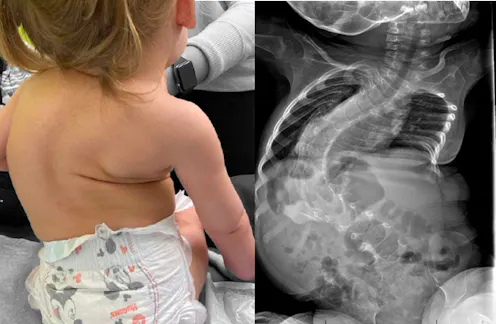

This causes the loss of muscular control that is the characteristic symptom of the disease – where, for example, babies with the most common spinal muscular atrophy, type 1, usually fail to reach the developmental milestones such as actively rolling, sitting or crawling that most of us, as parents, take for granted. Other, milder types of the disease appear later in childhood (types 2 and 3) or in young adults (type 4), and result in progressive loss of muscle function. Some adults with the disease, such as Michaela Hollywood, work to raise awareness of it.

To get Spinraza into motor neurons, the drug needs to be injected directly into the spinal column by lumbar puncture. Unpleasant at the best of times, this can be particularly challenging in older children and adults living with the disease, as spinal curvature is common. It also needs to be administered regularly: up to six injections in the first year of treatment at a cost of £75,000 per injection, and three each year after that.